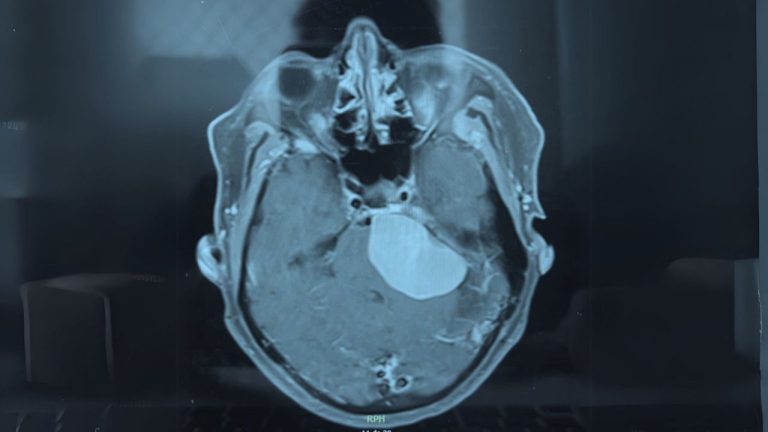

Os meningiomas são tumores que se originam das meninges, as membranas que envolvem o cérebro e a medula espinhal. Embora a…